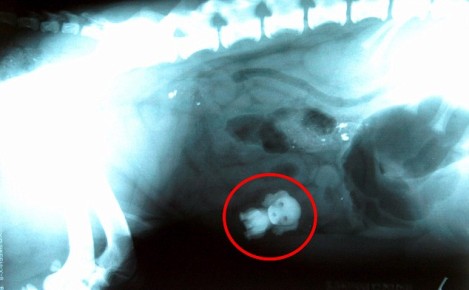

据猎狗的主人描述,阿尔菲近日来一直不吃不喝,还出现腹泻等症状,病得非常厉害。通过带它到兽医诊所进行X检查后发现,阿尔菲的肚子里有一只玩具小狗。主人表示,阿尔菲一定是趁自己不注意,溜入卧室,将玩具狗叼走并吞掉的。

经过几个小时的手术,玩具小狗已经从阿尔菲体内取出。如今,恢复正常的它兴奋得到处乱跑。